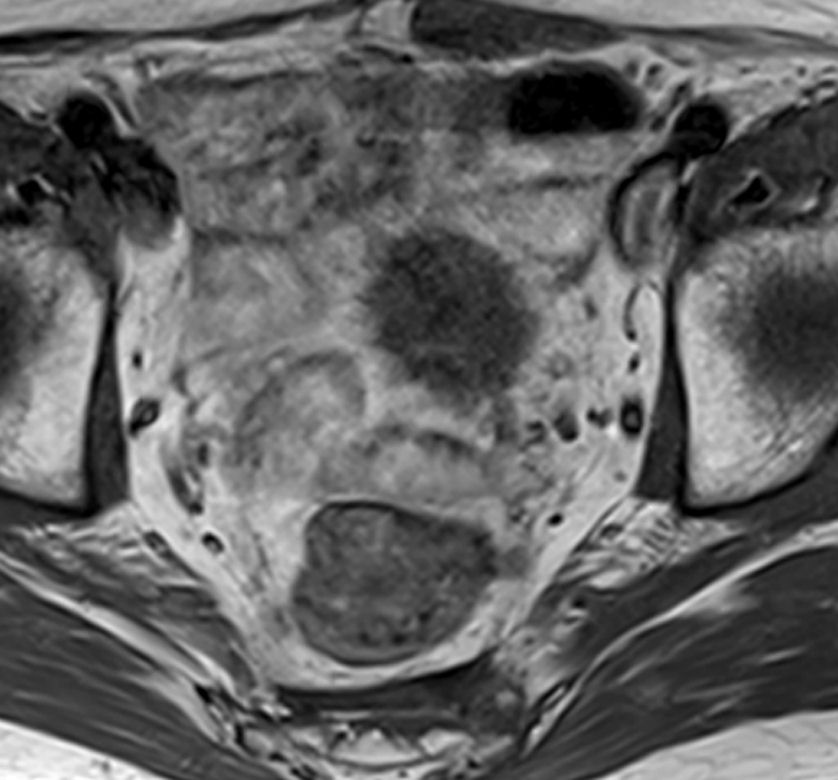

MRT einer inoperablen, die Harnblase infiltrierenden Metastase eines Colonkarzinoms, bei dem keine weitere systemische Therapie möglich war.